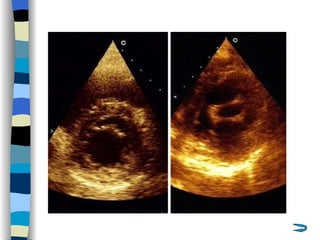

Echocardiography The most valuable technique for diagnosing MS, and determining its severity M-mode echo : Thickened, calcified leaflets open poorly, close slowly (EF slope ↓ ) The double peaks disappear Both leaflets move anteriorly during early diastole Two-dimensional echo: Fusion, thickening,  doming  of the valve leaflets, and poor leaflet separation in diastole;  mitral orifice area ↓

Doppler echo : Most accurate noninvasive technique for quantifying the severity of MS Spectrum Doppler: measure transvalvular gradient, MVA Color Doppler: display  high velocity color jet Provide other important information Cardiac chamber size (LA, RV) Left ventricular contractility Pulmonary arterial pressure Other coexisted valvular or congenital abnormalities  Mural thrombi